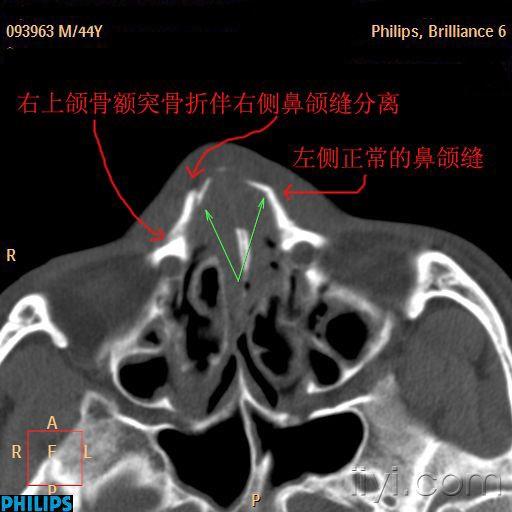

【急诊】颧骨骨折,上颌骨骨折ct表现